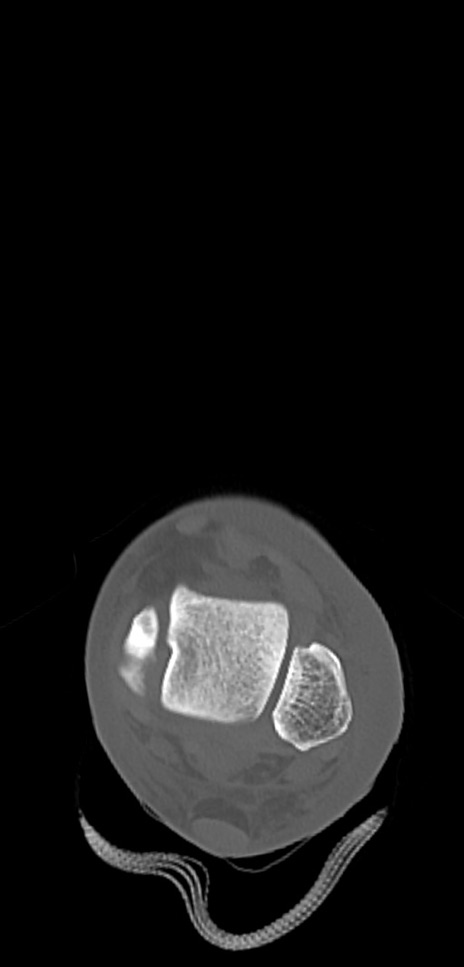

症例37 左足関節CT(横断像)

左足関節CT